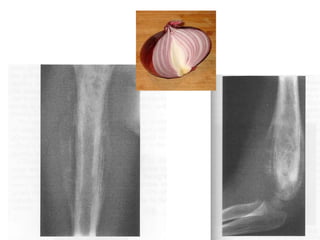

Plain Radiography

• Presents as extensive diaphyseal lesion

• At midshaft of the long bone, the cortex

displays increased density, extending

externally as periosteal new bone, forming

multiple thin parallel layers giving ‘onion peel

appearence’

• Periosteal reactions may also have codmans

triangle- lifting of periosteum from the bone.

• Ewing sarcoma appears as ill defined, permeative,

focally moth eaten, destructive intramedullary

lesion accompanied by a periosteal

reaction(onion skin)

• Lesion may have both lytic and sclerotic regions

• Extraosseous component is radiolucent with the

same density of soft tissue.